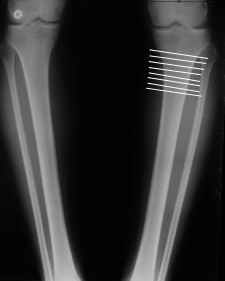

Вот, с учетом и без учета, и на разных уровнях...

Саша Артемьев, может, для данного случая свой вариант нарисуешь?